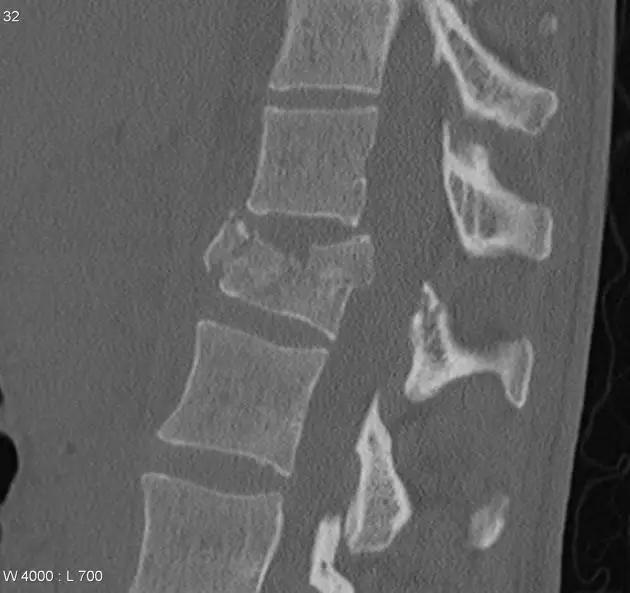

脊柱骨折

1. Burst 骨折

椎体轴向压力造成的骨折,通常发生骨折碎片向外侧的移位。可以发生在颈椎、胸椎或腰椎。

(来源:Radiopaedia)